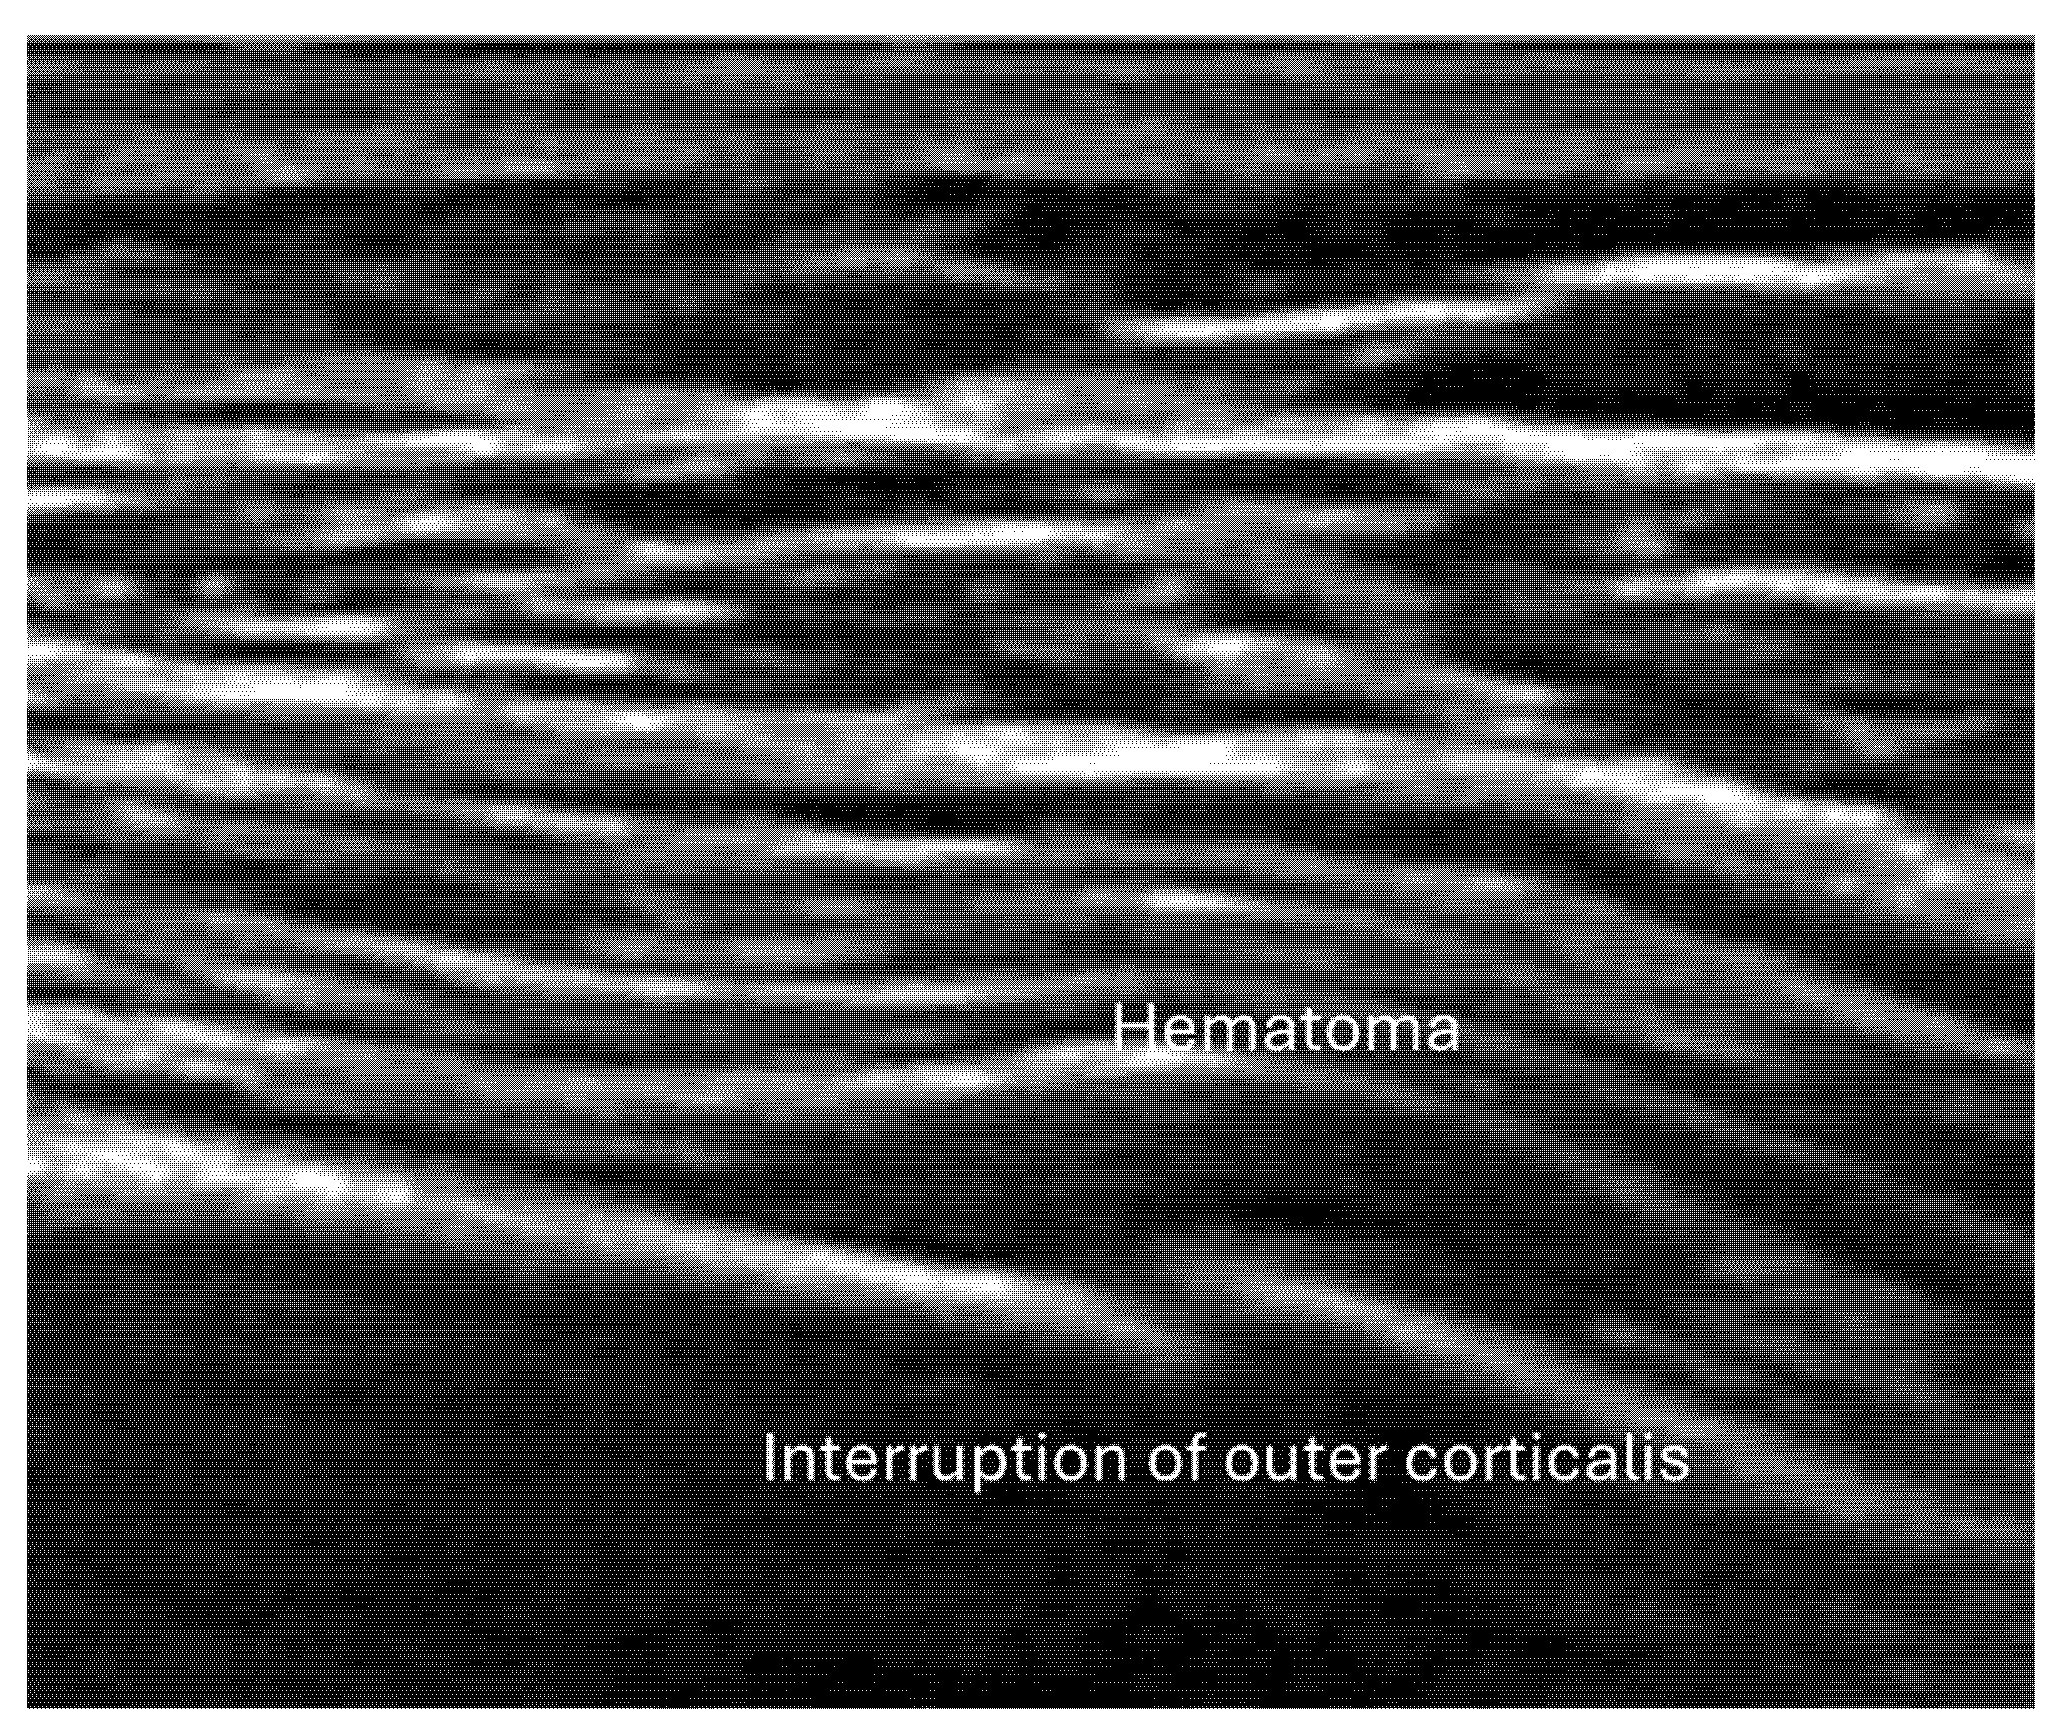

4.2. Sonoanatomy of Fractures [Figure 5, Figure 6, Figure 7 and Figure 8]

- Irregularity, interruption, or gaps in the cortical line: the cortical bone normally appears as a continuous, bright echogenic line, which is interrupted or irregular in the presence of a fracture.

- Local hematoma or soft tissue edema: fluid collections or increased echogenicity near the fracture site indicating bleeding and inflammation.